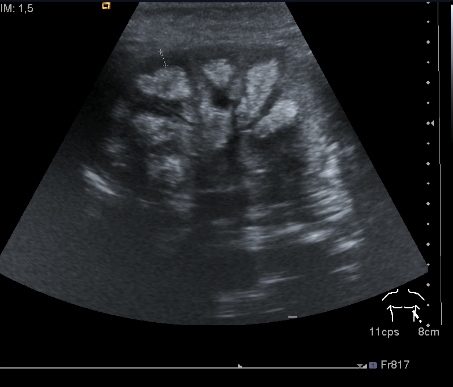

- Características: Los depósitos de calcio se localizan principalmente en las pirámides renales, especialmente en la papila renal. En las etapas iniciales, las ecografías muestran halos hiperecogénicos sin sombra acústica posterior alrededor de las pirámides medulares. A medida que la enfermedad progresa, pueden aparecer calcificaciones lineales, densas o puntiformes en la médula renal, con o sin sombra acústica posterior.

- Descripción: Halos hiperecogénicos rodeando las pirámides medulares, similares a guirnaldas o anillos.

- Características: No hay sombra acústica posterior.

2. Fase Intermedia

- Descripción: El depósito de calcio cubre completamente las pirámides, haciéndolas más hiperecogénicas.

- Características: Ausencia de sombra acústica posterior.

3. Fase Tardía

- Descripción: Marcada hiperecogenicidad de las pirámides con sombra acústica posterior evidente.

- Características: La ecogenicidad de la cortical renal permanece normal.